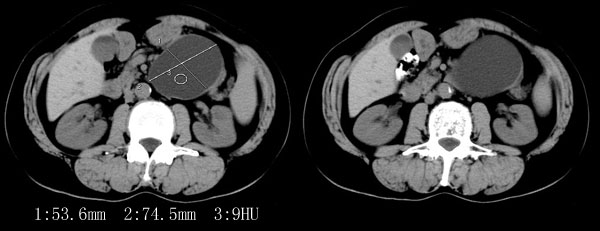

ct平扫加增强扫描:胆囊折叠,壁厚,其内见结石。胰腺体尾部见一5.8x7.5cm囊性肿物,ct值12hu,壁薄,增强扫描未明显强化,胰头不大,强化均匀。

ct诊断:1.胆囊炎,胆囊折叠并结石。

2.胰体尾部囊肿。